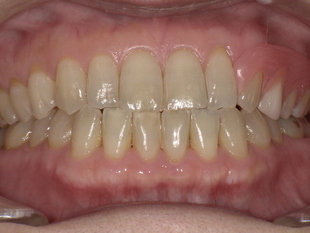

■ 【Before→After】ノンクラスプ義歯で口元の印象が大きく若返り

▼ 治療後(ノンクラスプデンチャー装着)

-

歯ぐきの色に馴染む樹脂で金具ゼロの自然な見た目

厚みが薄く、軽いため痛みほぼゼロの快適さ

義歯のフィット感が高く、噛む力も安定

口元がふっくらし、見た目・印象が10歳以上若返る

患者様からは、

「友達にも入れ歯だと気づかれなかった!」

「痛くない入れ歯は初めてで驚きました」

という喜びの声をいただきました。